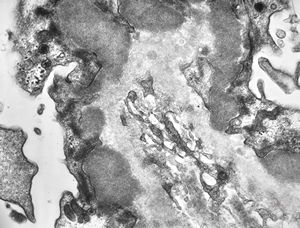

M,37y. | type I membranoproliferative glomerulonephritis (mesangiocapillary)